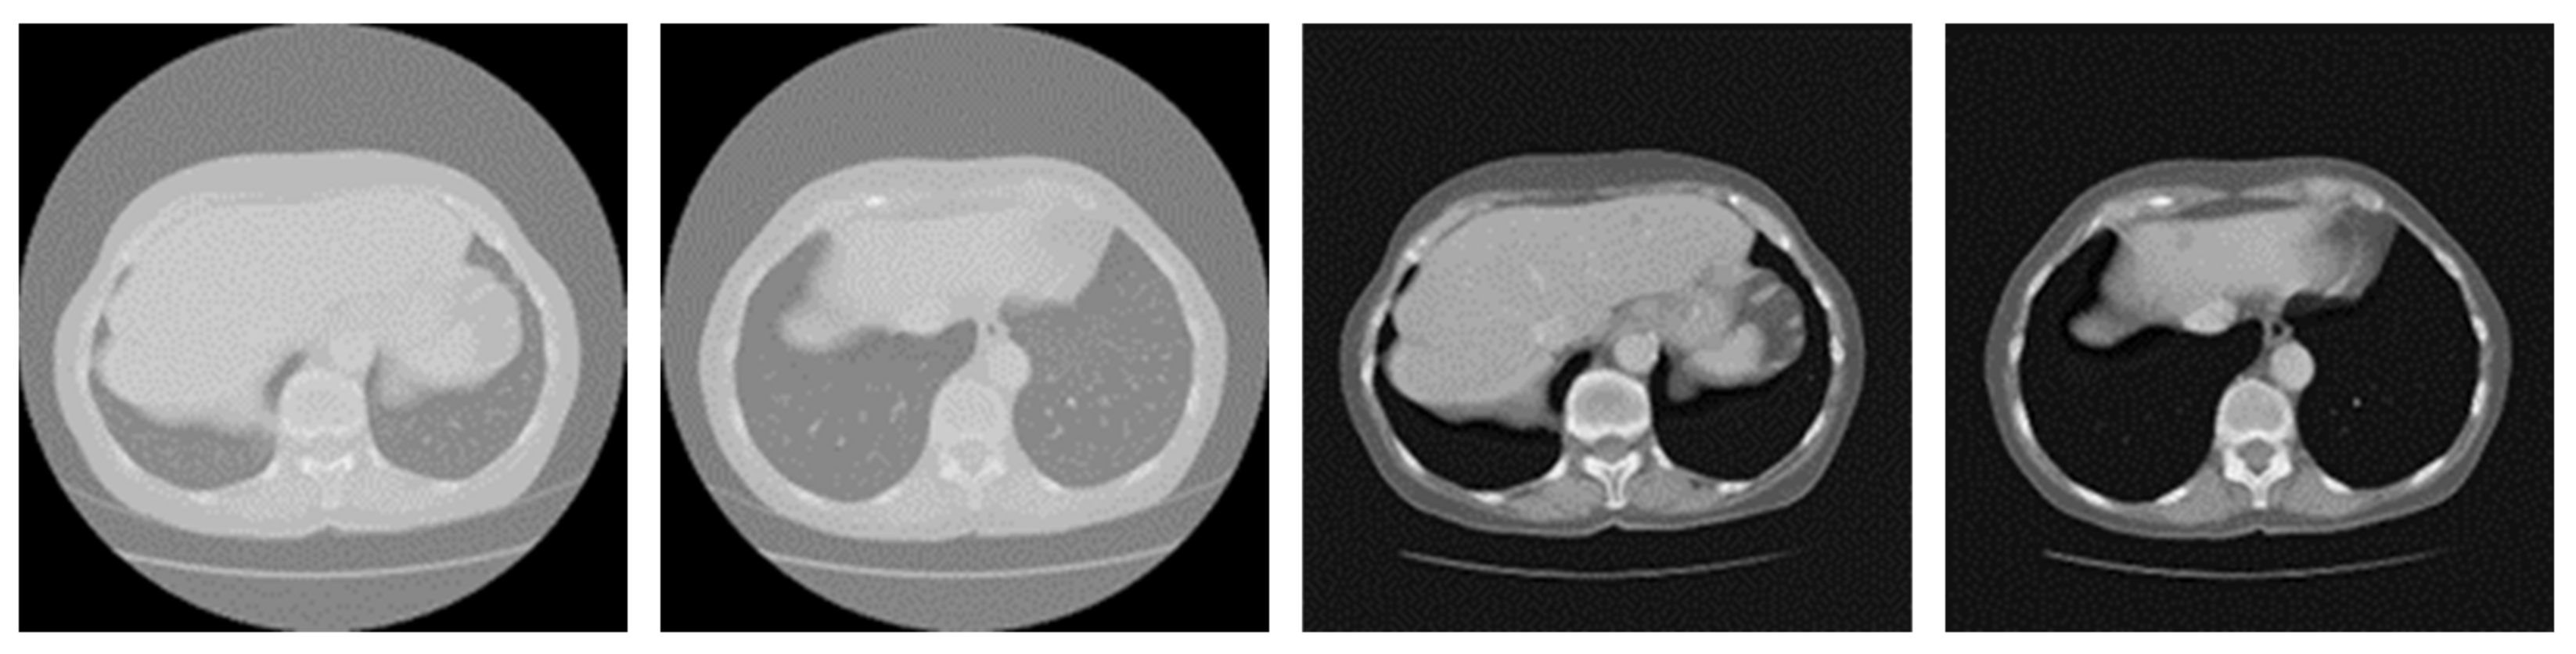

3.2. Preprocessing

4.1. Dataset and Implementation Details